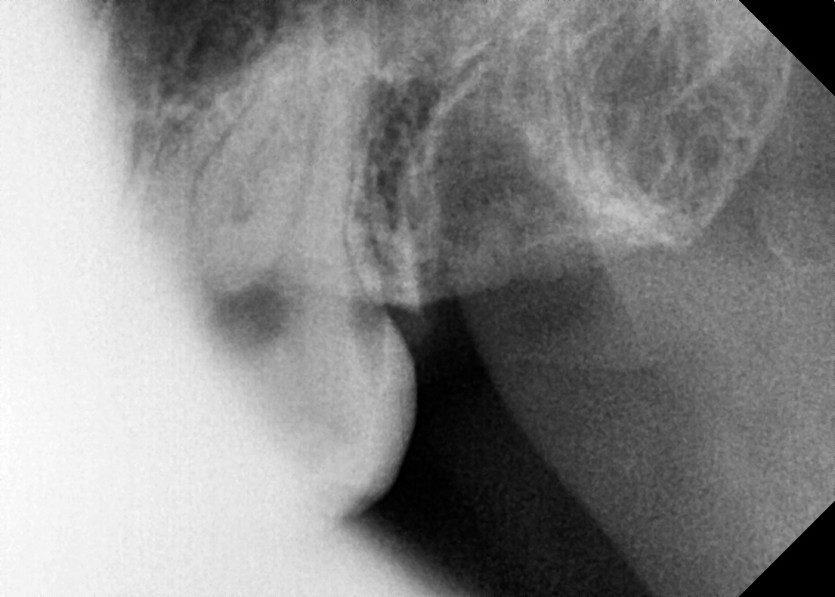

#28,38 사랑니 발치

구강 외과 전문의가 당일 발치했습니다.